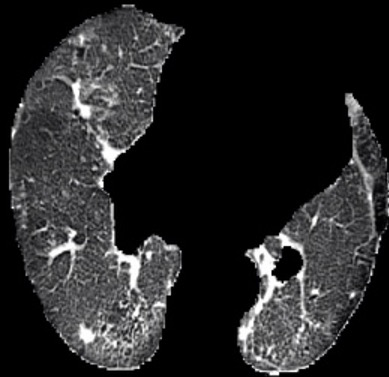

In the field of medical imaging, particularly in tasks related to early disease detection and prognosis, understanding the reasoning behind AI model predictions is imperative for assessing their reliability. Conventional explanation methods encounter challenges in identifying decisive features in medical image classifications, especially when discriminative features are subtle or not immediately evident. To address this limitation, we propose an agent model capable of generating counterfactual images that prompt different decisions when plugged into a black box model. By employing this agent model, we can uncover influential image patterns that impact the black model's final predictions. Through our methodology, we efficiently identify features that influence decisions of the deep black box. We validated our approach in the rigorous domain of medical prognosis tasks, showcasing its efficacy and potential to enhance the reliability of deep learning models in medical image classification compared to existing interpretation methods. The code will be publicly available at https://github.com/ayanglab/DiffExplainer.